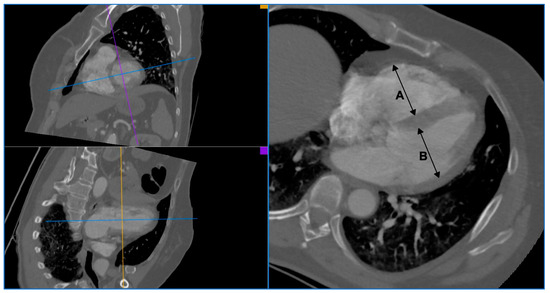

| enlargement of the right ventricle | right ventricle diameter to left ventricle diameter ratio (RV/LV) in CTA ≥ 0.9 | I: enlarged right ventricle (RV/LV ≥ 0.9) J: non-enlarged right ventricle (RV/LV < 0.9) | I: 27 J: 34 |

| RV diameter [mm] | 49.55 | 14.33 |

| LV diameter [mm] | 51.66 | 8.77 |

| RV/LV | 0.96 | 0.23 |